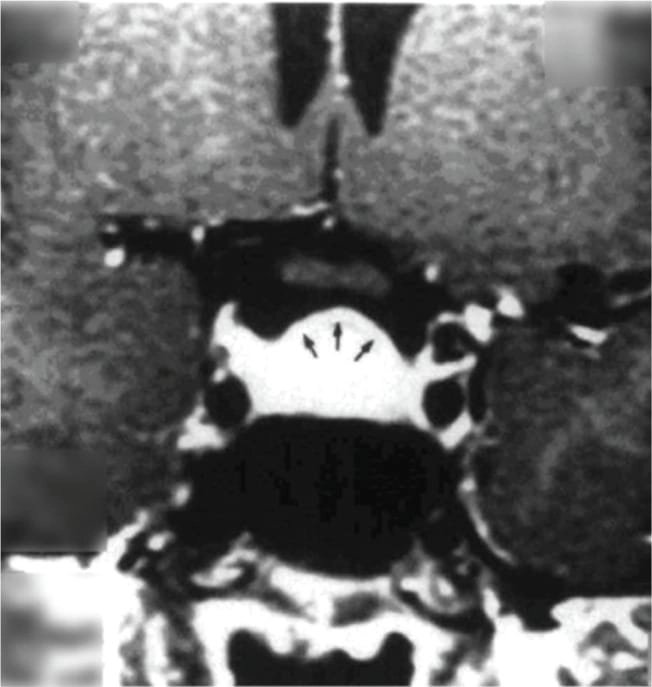

তবে পিটুইটারি হাইপারপ্লাসিয়া দেখা যায় প্রাইমারি গনাডাল, অ্যাডরিনাল বা হাইপোথাইরয়েডিজমের মত এন্ড অর্গান ইনসাফিসিয়েন্সিতে। বিশেষ করে, অব্যবহৃত প্রাইমারি হাইপোথাইরয়েডিজমে পিটুইটারি হাইপারপ্লাসিয়া পূর্বের ধারণার তুলনায় অনেক বেশি দেখা যায়। ২০১৯ সাল পর্যন্ত এরকম ১০৫টি কেস রিপোর্ট করা হয়েছে। এই ধরনের হাইপারপ্লাসিয়া গম্বুজ-আকৃতির (dome-shaped) হয়ে অপটিক কায়াজমাকে চেপে ধরতে পারে, যার ফলে অপারেশনের প্রয়োজন পড়তে পারে—যেমনটা আমাদের তৃতীয় কেসে ঘটেছিল।

চিকিৎসক তথা আবিষ্কারক সত্যম তিনটি কেসের বিষয় নিয়ে যখন তুলনা করতে নিলেন এবং পুরনো সৃষ্টি ঘাটতে শুরু করলেন তখন তিনি দেখতে পান সবগুলি ক্ষেত্রেই একই রকম সাদৃশ্য অর্থাৎ পিটুইটারি গ্রন্থি মাঝের অংশ এই গ্রন্থি দেখতে খানিকটা প্রজাপতির মতোই এবং তার মাঝের অংশের (প্রজাপতির দেহের উপরের অংশ মাথার মতই দেখতে) উপরের ভাগ সব ক্ষেত্রেই ডোমের মত বা গম্বুজ আকৃতির। তিনি এই ডোম বা গম্বুজ আকৃতি হওয়ার কারণ বিশ্লেষণ করতে গিয়ে দেখেন পিটুইটারির সামনের অংশ যেখানে থাইরোট্রপগুলো থাকে, যেখান থেকে এই টিউমারটি হয়। আর যখনই এটি বাড়বে তখন টমের মতনই তৈরি হবে। অর্থাৎ গম্বুজ আকৃতির। আর সেখান থেকেই ডোম-সাইনের উৎস অর্থাৎ আবিষ্কার।

MRI-তে এই হাইপারপ্লাসিয়া সাধারণত গম্বুজ-আকৃতির ও সমমিত হয় এবং হোমোজেনাস সিগনাল ইন্টেনসিটি দেখায়, যেখানে সাধারণ নন-ফাংশনাল পিটুইটারি অ্যাডেনোমা নানা আকার ও অসমতা নিয়ে দেখা যায়।

পূর্ববর্তী গবেষণাগুলিও এই ‘Dome Sign’-এর গুরুত্ব তুলে ধরেছেন, যেমন ডঃ আহমেদ (১৯৮৯), ডঃ সারলিস (২০০০), ডঃ ফ্রান্সেস্কি ও পাসেরি (২০১১) এবং ডঃ শুক্লা (২০১৯)। এসব গবেষণায় MRI-তে ডোম-আকৃতির হাইপারপ্লাসিয়া শণাক্ত হয়েছে যা লেভোথাইরক্সিন চিকিৎসার মাধ্যমে কয়েক সপ্তাহের মধ্যেই হ্রাস পেয়েছে।

তাঁর দাবি, MRI-তে ‘DOME Sign’ থাকা এবং TSH বাড়তি থাকলে, সেটি হাইপোথাইরয়েডিজম-জনিত হাইপারপ্লাসিয়ার সম্ভাবনার কথা নির্দেশ করে এবং এই রোগীদের শুধুমাত্র লেভোথাইরক্সিন দিয়ে চিকিৎসা করলে পূর্ণ আরোগ্য সম্ভব।